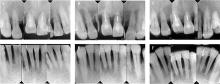

Zhang CR, Liu Q, Yang JW, et al. A digital technique for splinting periodontally compromised mobile teeth in the mandibular anterior region[J]. J Prosthet Dent, 2021, 125(4): 560-563.

Wang ZY, Guo LH, Deng K, et al. Additively manufactured zirconia periodontal splint integrated prosthesis: A proof-of-concept[J]. J Dent, 2025, 156: 105701.

Liu YC, Bai SZ, Zhong S, et al. Digital workflow for periodontal splinting with a guided device[J]. J Esthet Restor Dent, 2023, 35(4): 621-624.